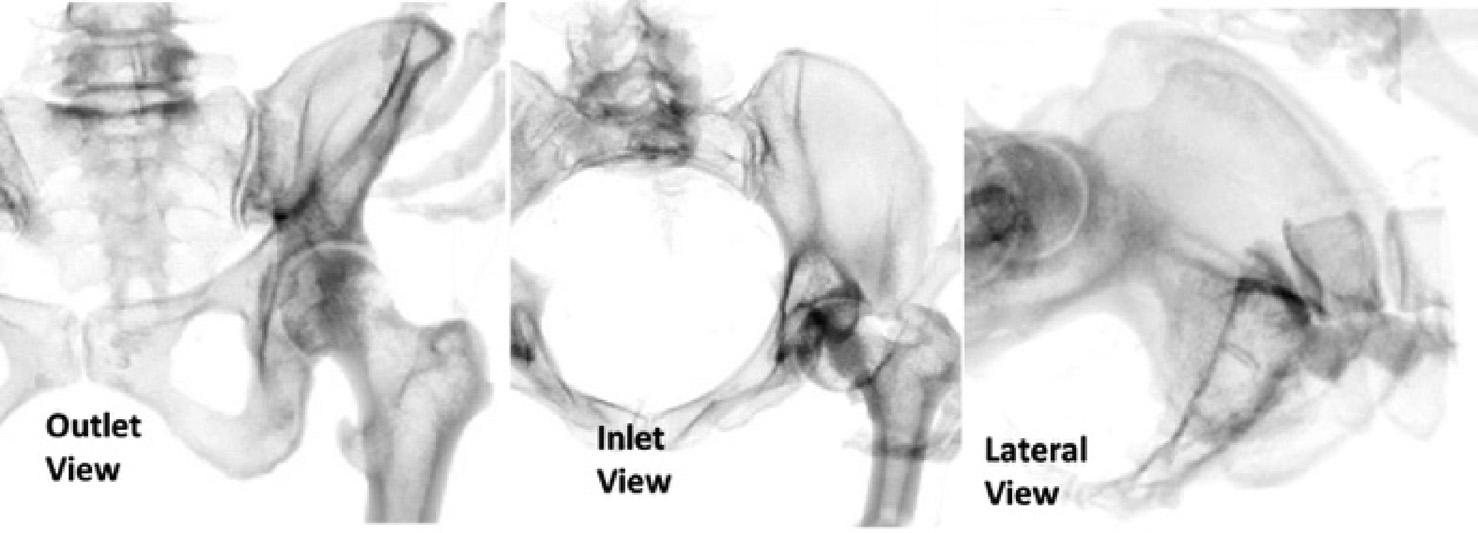

为了向住院医师显示正确的图像,对模拟器的软件进行了调整。使用可视人计划的CT数据VR 1生成了该手术中使用的透视图像(图6)。该手术使用三个主要透视视图:出口视图、入口视图和侧位视图。入口视图和出口视图是用于引导导丝导航的主要视图。这两个视图相对于患者处于斜角,使得导丝轨迹和必要调整难以判断。学会在这两个视图中正确评估导丝轨迹被认为是该手术的主要技能之一。